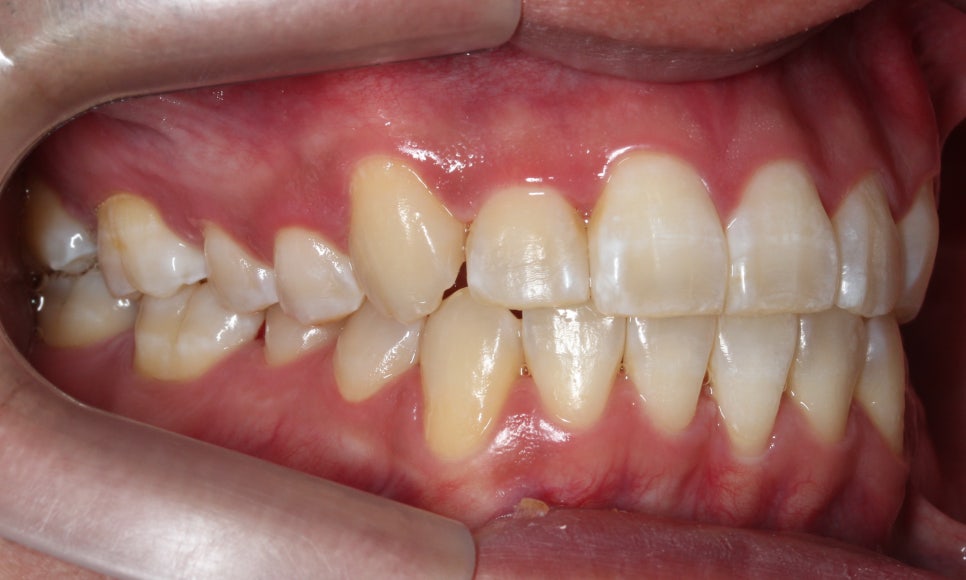

이번에는 덧니 고민으로 오신 환자분인데요.

윗니 오른쪽 두 번째 앞니가 들어가 있고,

다른 앞니끼리도 너무

세게 닿아서 고민이라고 오셨어요.

사진을 보실 땐

눈에 보이는 방향의 왼쪽이

환자에게는 오른쪽입니다.

#12 치아는 안으로 들어가 있었습니다.

환자분은 #13 이 튀어나왔다고 생각하시던데,

이렇게 씹는 면 사진으로 보면

#13이 튀어나왔다라기보단

#12가 상대적으로 들어가 있는 게 맞죠.